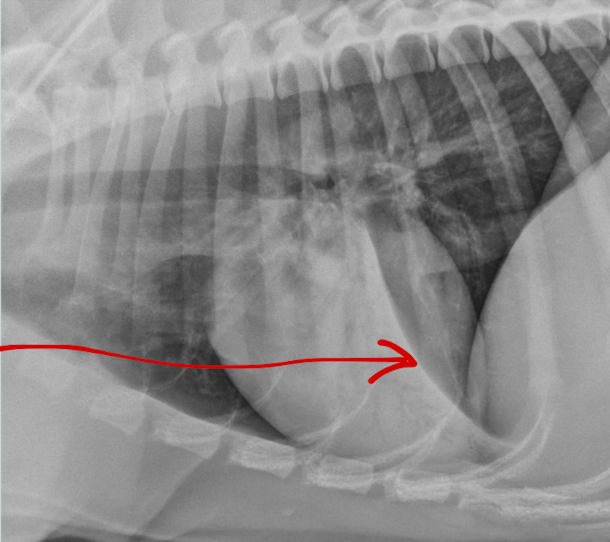

What is the arrow pointing to?

large osteophyte on the anconeal process (earliest change seen in DJD)

osteophyte on the medial coronoid process in elbow DJD